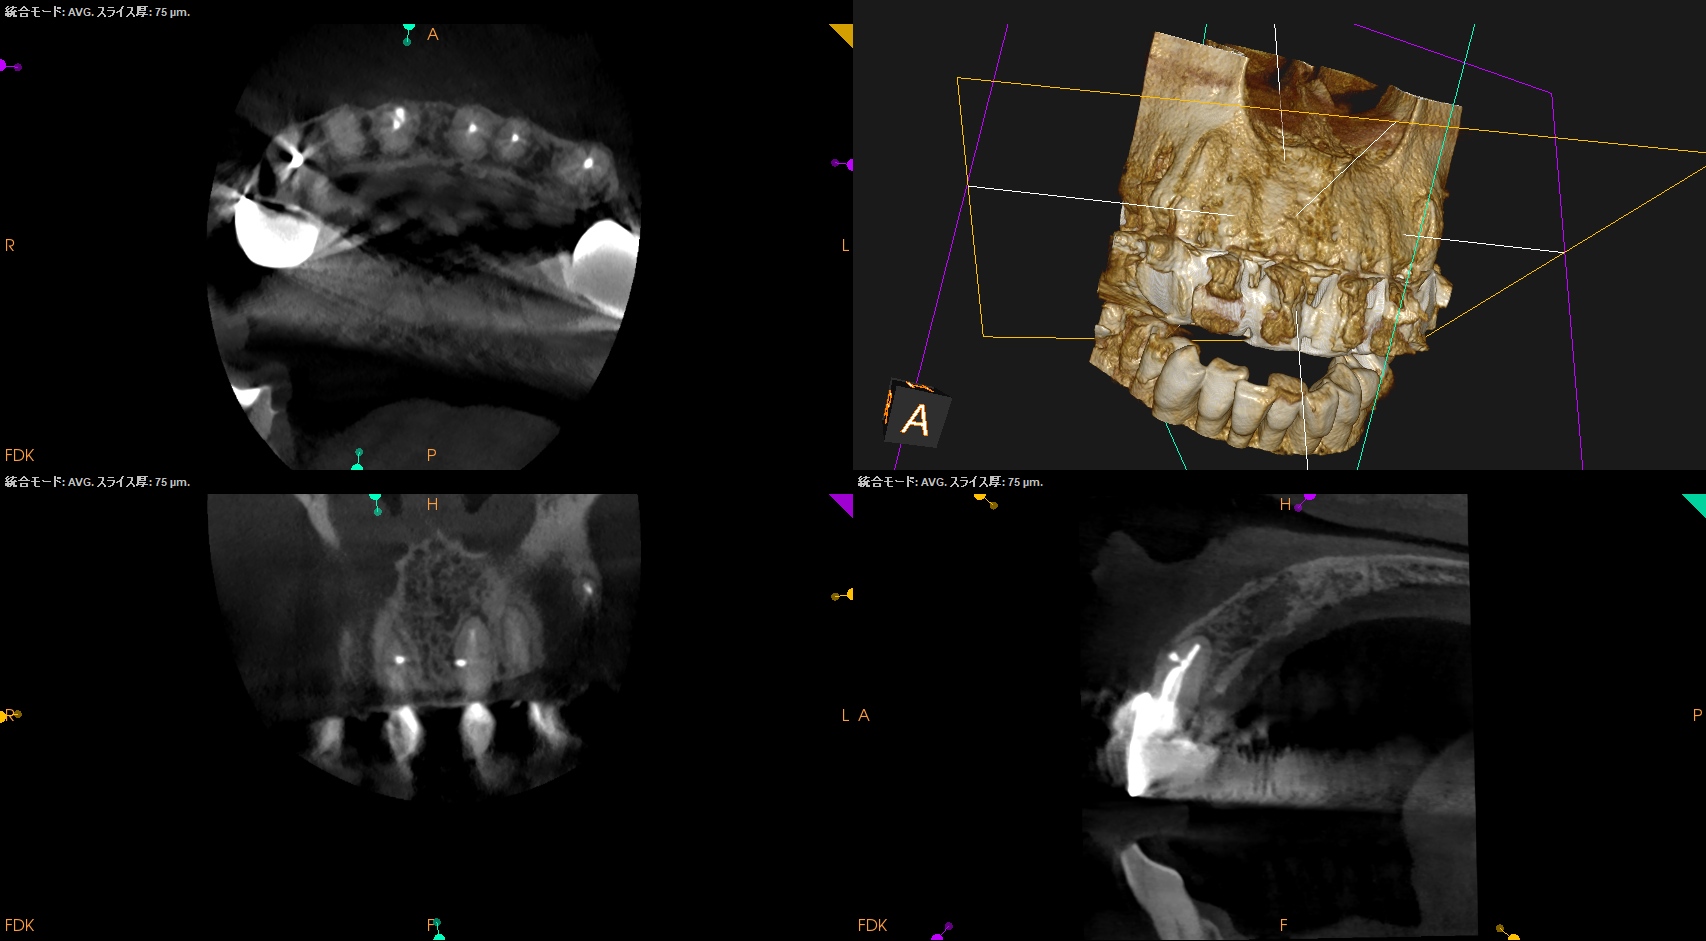

#8,9 Microsurgery 1yr recall(2026.3.11)

#8,9(B)

初診時と比較した。

問題は大きく解決されている。

初診時のSinus tract, 臨床症状は消失した。

ということでこの2歯をこれ以上経過を見ていく必要はないだろう。

この日で終診とさせていただいた。